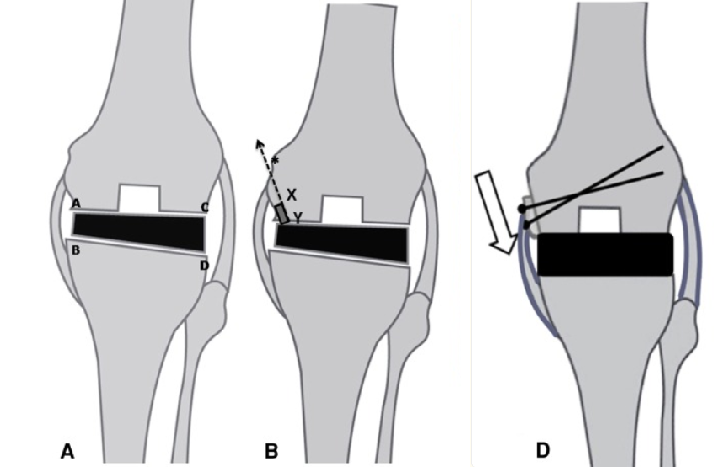

这时,提前准备的 “内侧髁滑移截骨术” 派上了用场。

杨德金在内侧股骨髁远端做了有限的滑移截骨,既没伤到韧带、关节囊这些关键稳定结构,又通过精准调控滑移量,慢慢把关节间隙 “撑开” 了。

这种方法特别适合骨性畸形、内侧瘢痕粘连的复杂病例,创伤小、恢复稳。